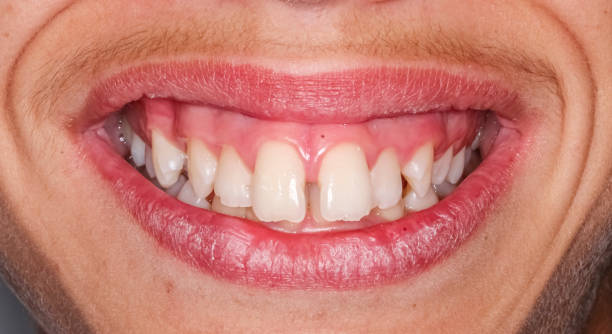

Triángulos negros y stripping: relación y prevención

Los triángulos negros son los espacios oscuros que aparecen entre los dientes a nivel de las encías, donde la papila gingival no rellena completamente el espacio interdental. Son un problema estético frecuente y una de las preguntas que más preocupa a los pacientes antes de iniciar un tratamiento de ortodoncia.

El stripping tiene una relación directa con los triángulos negros en dos sentidos opuestos:

El stripping puede provocar triángulos negros si se realiza en exceso o de forma inadecuada. Al reducir demasiado el punto de contacto entre dos dientes, puede crearse un espacio que la encía no cubre, especialmente en pacientes con dientes de forma triangular o con papila gingival baja.

El stripping puede eliminar o reducir triángulos negros cuando se usa de forma estratégica para recontornear la zona de contacto. Al dar una forma más cuadrada al área de contacto interproximal, se reduce o elimina el espacio oscuro visible.